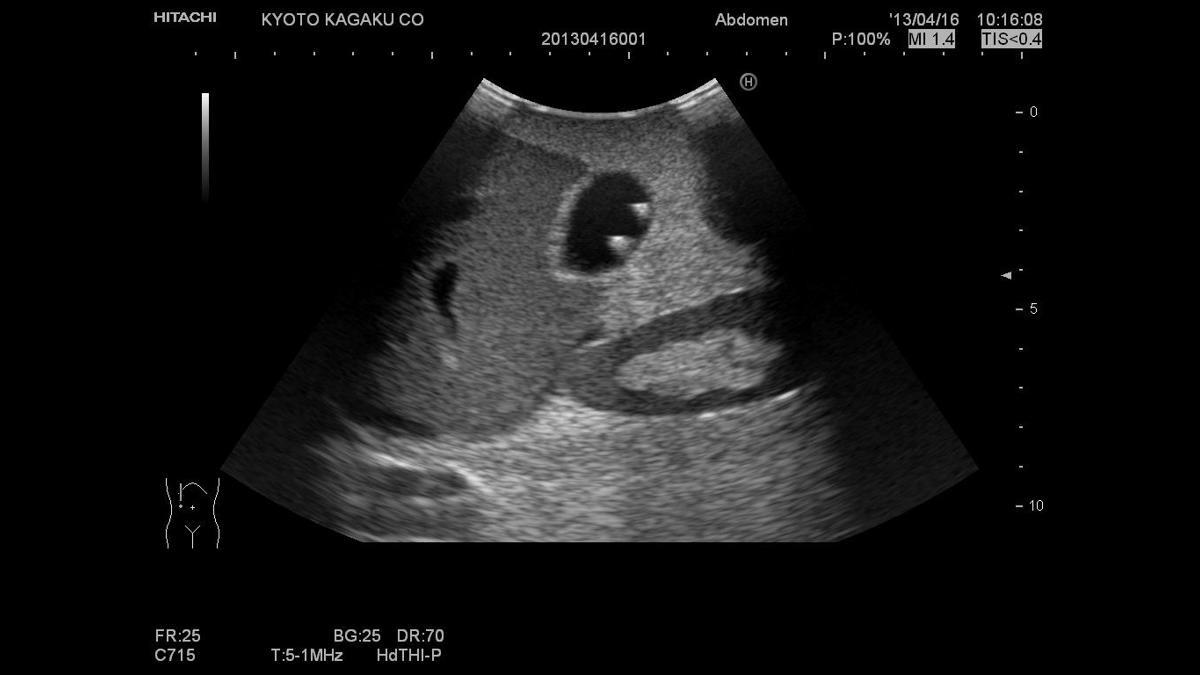

The Paediatric FAST/Acute Abdomen Phantom facilitates the practice of hands-on training using ultrasound to examine young patients. Using FAST procedures, trainees are able to identify internal haemorrhage at the perihepatic, perisplenic, pelvis, and pericardium area, whilst the ultrasound capabilities of the module allow for bowel intussusception, appendicitis and biliary dilatation recognition.

Using FAST procedures to identify Internal hemorrhage at the perihepatic, perisplenic, pelvis, and pericardium area